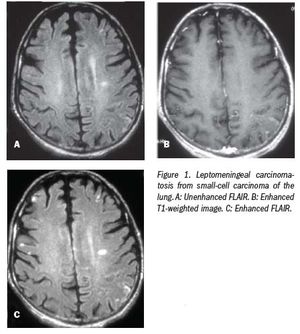

Contrast-enhanced FLAIR is more sensitive than other MRI techniques due to T2 prolongation and T1 shortening.

When considering which is the most sensitive MRI technique for detecting disease in the brain, the choice is usually between contrast-enhanced T1-weighted imaging and T2-weighted fluid-attenuated inversion recovery (FLAIR) imaging.